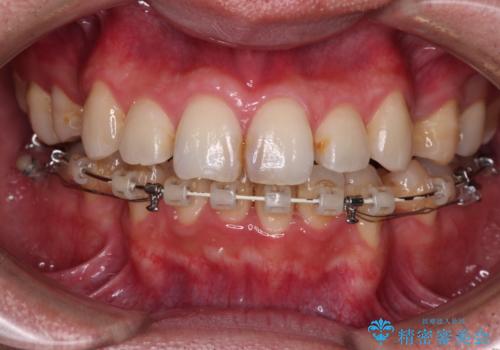

- 矯正装置

- ハーフリンガル

裏側装置での交叉咬合改善は非常に困難なもので、頻繁に装置の脱落がありました。

それでも想定以上に治療期間は長期化せず、咬み合わせも口元も満足のいく仕上がりとなりました。